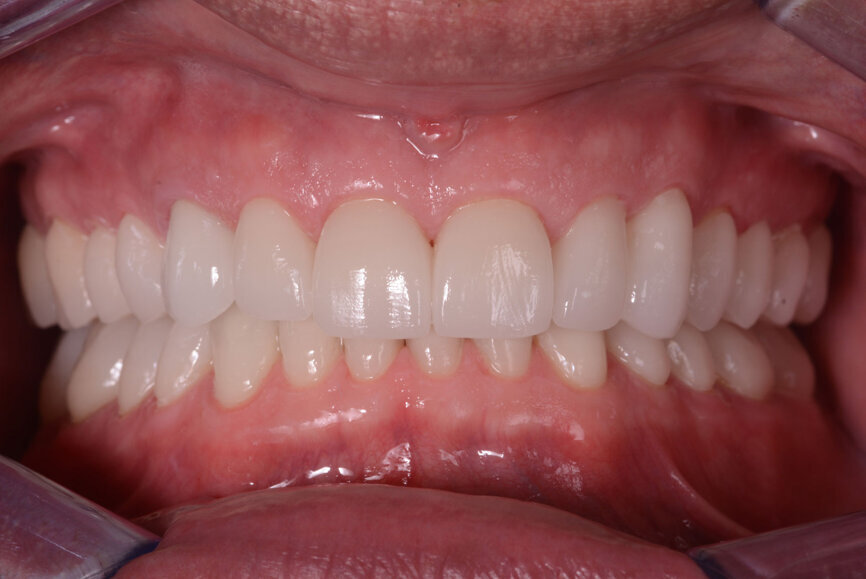

The crowns (#11–13 and 21–23) and veneers (#14–17, 24–27, 31–37 and 41–47) were secured to the abutments using a light-cured resin adhesive (Futurabond U and Bifix QM, VOCO). A high-performance LED light-curing device (Celalux 3, VOCO) was used for polymerisation (Figs. 11 & 12).

Excess luting material was removed, and the occlusion was adapted and checked with the T-Scan technology (Tekscan). A removable acrylic resin splint was used to protect the final restorations. The final restorations were checked after six months. The restorations were still stable and showed no signs of fracture (Figs. 13–15). The patient also reported that he no longer suffered from headaches with the new bite height.

Fig. 13: Intraoral photographs after treatment.

Figs 14: Intraoral photographs after treatment.